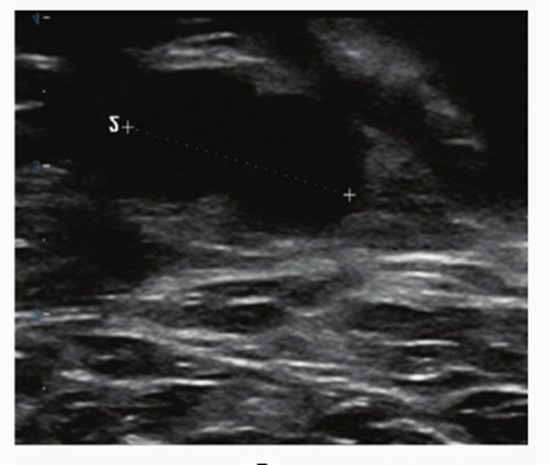

Methods and results: A blinded radiologist retrospectively analyzed 109 IDC cases using the American College of Radiology (ACR) Breast Imaging Reporting and Data System (BI-RADS) classification, evaluating ultrasound features such as lesion shape, margins, orientation, echo pattern, calcifications, vascularity, and lymph node involvement. Tumors were graded histologically (Scarff-Bloom-Richardson system) as low (grades 1 and 2) or high (grade 3). Immunohistochemistry determined estrogen receptor (ER), progesterone receptor (PR), human epidermal growth factor receptor 2 (HER2), and Ki-67 status. ER and PR positivity were defined as > 10% nuclear staining, HER2 graded on a 0-3+ scale, and Ki-67 positivity as ≥ 10% staining. Statistical analyses, including logistic and linear regression, examined correlations between ultrasound features and histological/molecular profiles. Among 109 women (mean age 48.4 ± 12.5 years), the mean tumor length and width were 21.83 ± 11.22 mm and 15.3 ± 6.97 mm, respectively. Histopathological grading revealed that grade 2 tumors were predominant (51%), while grade 1 and grade 3 tumors were observed in 25% and 24% of cases, respectively. ER and PR positivity were observed in 76.4% and 67.6% of cases, respectively. High-grade tumors were significantly associated with ER and PR negativity (p-value < 0.05). Ultrasound features associated with high-grade tumors included larger tumor length (p-value = 0.029). ER positive tumors had smaller axillary lymph nodes (p-value < 0.05). Likewise, PR positive tumors exhibited smaller suspicious axillary lymph nodes compared to PR negative cases (p-value = 0.004).